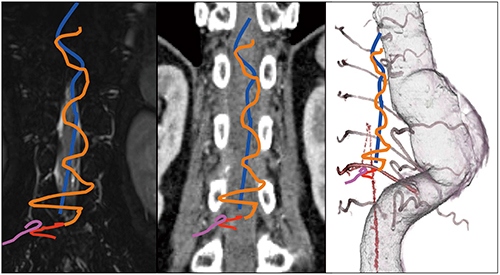

撮影終了直後はAZE社のWSは導入されておらず,神経内科による第一次カンファレンスでは,d-AVFが考えられる血管の蛇行はあるが,流入血管ははっきりしない状態であるとコメントされていた。検査終了の2週間後にAZE社のWSが導入され,非剛体サブトラクション処理を行ったところ,動静脈の画像が鮮明に描出された(図4,5)。脳神経外科医よりd-AVFを疑う3D画像であると指摘され,診断アンギオ画像と3D画像との一致する所見情報により,IVR治療が検討され,血管内治療のシミュレーションが行われた(図6)。

図5 AZE社製WSによる非剛体サブトラクション処理画像

図6 診断アンギオから術前シミュレーションした3D画像